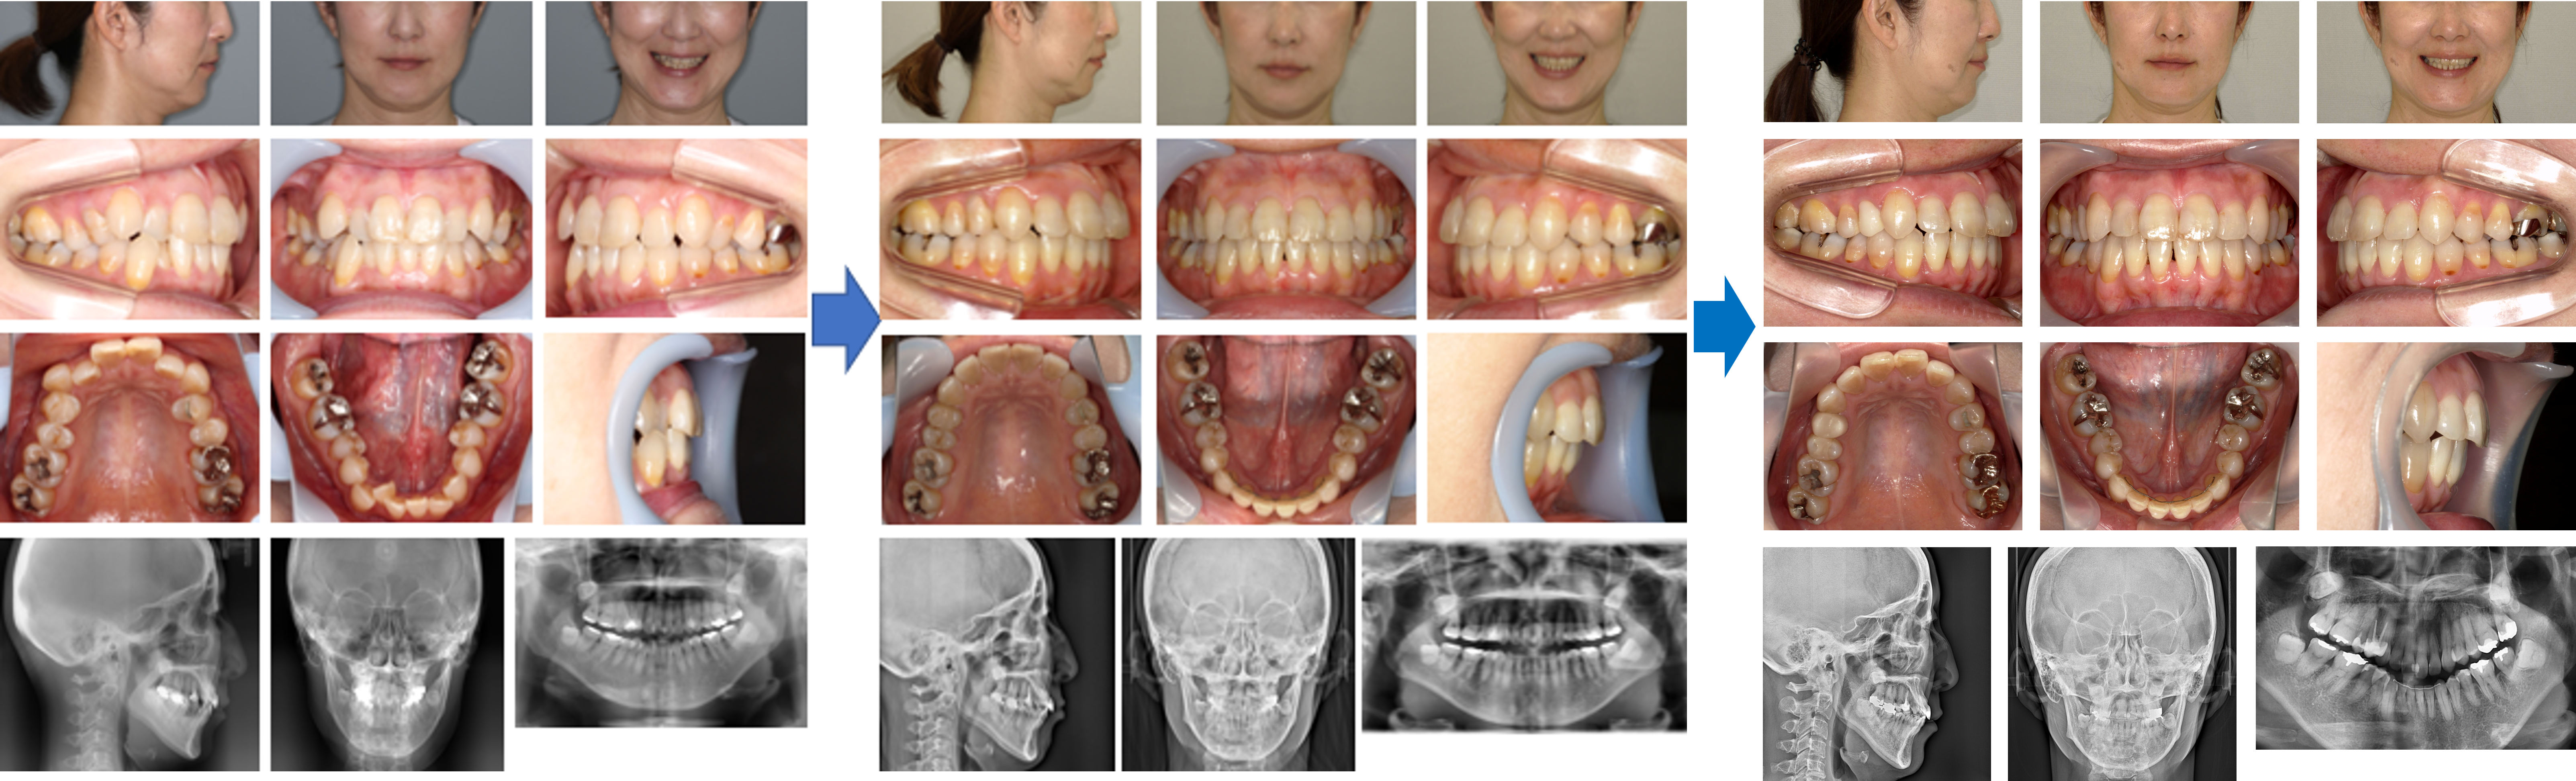

【治療例】初診時年齢:22歳4か月 / 性別:女性 / 主訴:前歯が出ている。もっと笑顔が作れるようになりたい。

症例の概要:この症例は左側上顎中切歯の突出による口唇閉鎖不全を主訴に来院された。上顎の歯列弓はV字歯列弓で上顎前歯部は重なっていたため、上顎両側側切歯を抜歯し上顎前突の改善を図った。その結果、上下歯列の正中線が一致したほか、口唇閉鎖が容易になった。

主訴:前歯が出ている。もっと笑顔が作れるようになりたい。

診断名:上顎V字型歯列弓を伴った上顎前突症例

使用した主な装置:咬合挙上版、マルチブラケット装置

抜歯/非抜歯および抜歯部位:抜歯(上顎両側側切歯)

治療期間:3年5か月

治療回数:45回

リスクの副作用:歯の移動や抜歯による違和感や疼痛、口内炎、歯肉退縮、歯根吸収が生じることがある